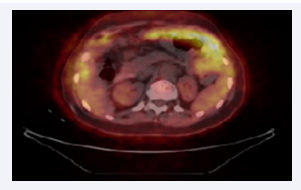

The control PET/CT after 6 cycles of treatment showed partial therapeutic response in terms of size and metabolic activity of peritoneal carcinomatosis, a significant to complete reduction in the volume of ascites and peristension of the known multiple disseminated bone lesions, which were without significant morphological dynamics (Figure 2).

After six cycles seventh line.

Figure 2: After six cycles seventh line.